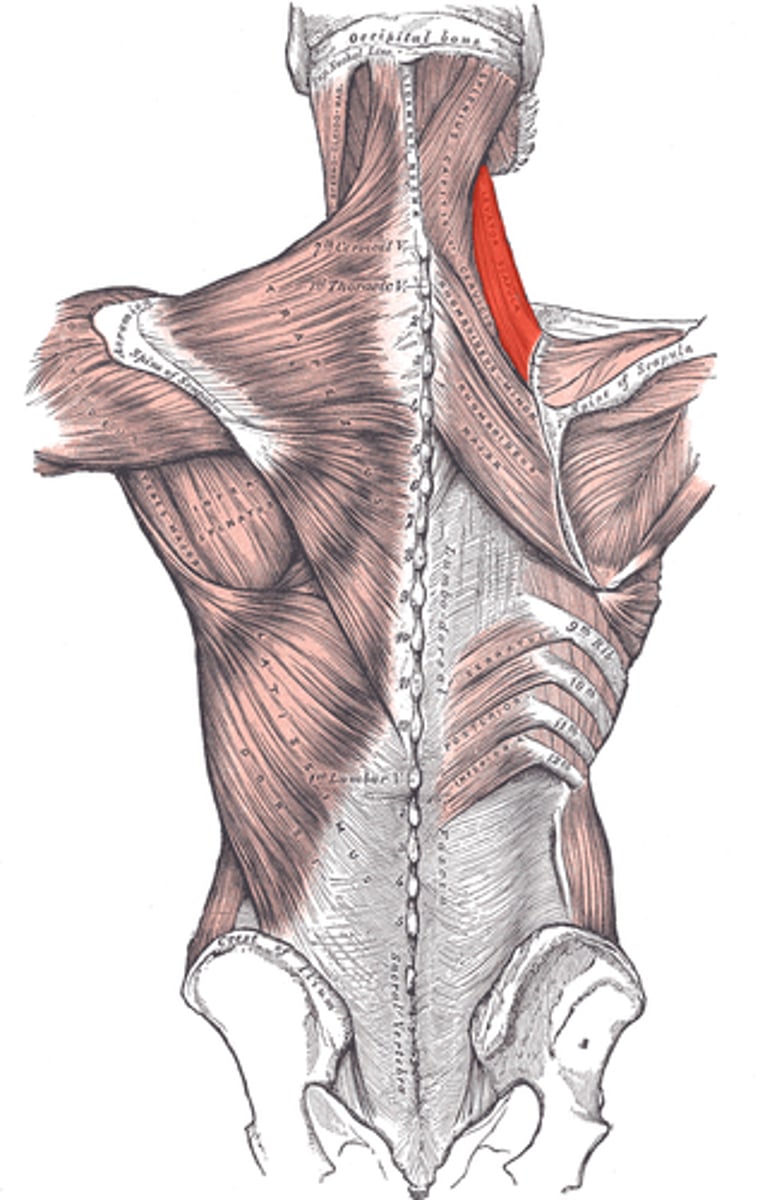

(Posterior axioappendicular and scapulohumeral muscles:) Superficial posterior axioappendicular muscles (extrinsic shoulder)

Trapezius and Latissimus dorsi

(Superficial posterior axioappendicular muscles (extrinsic shoulder):) Trapezius

-Elevates, depresses, and retracts scapula

-Accessory nerve (CN XI)